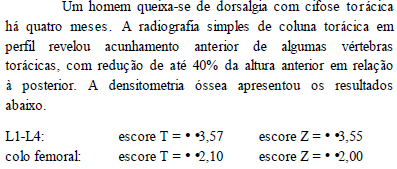

As imagens acima são de um mesmo paciente. Considerando essa imagens e os achados por elas revelados, julgue os itens subseqüentes.

O músculo ilíaco direito apresenta aspecto normal, sem evidências de abscesso.

Há um grande abscesso pélvico.

A tomografia foi realizada sem contraste venoso.